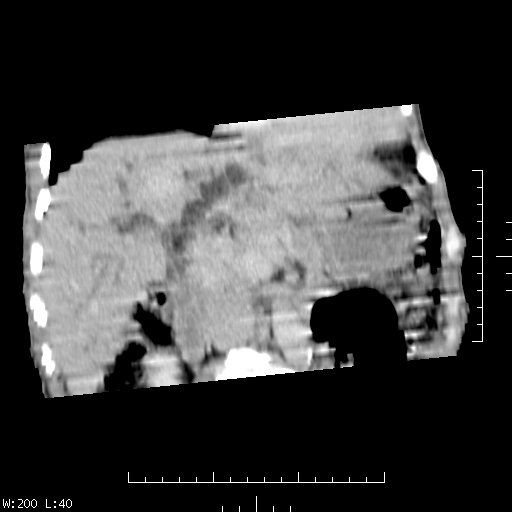

男,47岁,上腹部疼痛食欲不振年余,全身黄染两月.查:消瘦,hb5-6g.请会诊.

本例肠道准备欠佳,增强扫描时机抓得不好,给鉴别诊断带来困难,肝内胆管扩张,增强扫描胆总管上段壁结节样强化,十二指肠区环形软组织影增强明显强化,内有肠内容物,大家意见惊人的一致,考虑十二指肠恶性肿瘤累及肝总管, 我认为肝门部胆管癌不能排除。